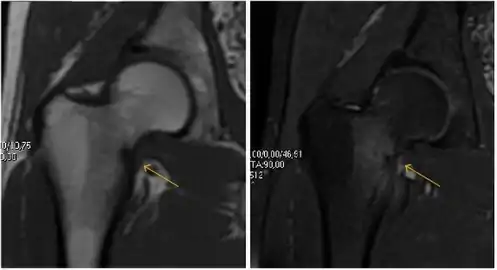

Most of the angles and measurements described in the plain radiograph section can be accurately reproduced on MRI. In addition, the superiority of MRI resolution with intra-articular contrast allows detection of labral and chondral abnormalities that may influence the choice of medical, percutaneous, or surgical management (Figure 9).[1]

Figure 9:

Sagittal T1 weighted image showing anterosuperior labral tear.[1]

Sagittal T1 weighted image showing chondral lesion.[1]

MR arthrography has proven superior in accuracy when compared to native MR imaging. It is considered the best technique to assess the labrum. Knowledge of the normal variable morphology of the labrum helps to differentiate tears from normal variants. A triangular shape is most commonly seen in 66% of asymptomatic volunteers, but round, flattened, and absent labra can also be found in asymptomatic populations. MR arthrography has demonstrated sensitivity over 90% and specificity close to 100% in detecting labral tears. Loose bodies are demonstrated as filling defects surrounded by the hyperintense gadolinium.[1]

Association between labral tears and chondral damage has been demonstrated. This underscores the interaction between cartilage and labrum damage in the progression of osteoarthritis. Chondral damage to the posteroinferior part of the acetabulum as a contrecoup lesion occurs in approximately one-third of pincer cases secondary to persistent abutment on the anterior part of the joint leading to a slight posteroinferior subluxation. This is considered a bad prognosis sign.[1]